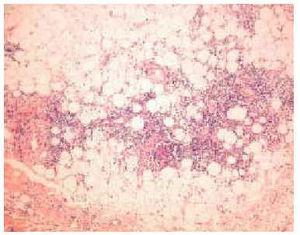

En septiembre de 1999 presentó un nuevo brote de lesiones cutáneas clásicas de dermatomiositis, así como 5 lesiones nodulares en ambos miembros superiores, de unos 3 cm de diámetro, dolorosas, induradas, de superficie poiquilodérmica, sin sintomatología muscular ni elevación de las enzimas musculares. Se realizó una biopsia cutánea de un nódulo del brazo que puso de manifiesto una degeneración vacuolar focal de la capa basal epidérmica y un leve infiltrado inflamatorio linfohistiocitario perivascular en la dermis. Lo más llamativo fue la presencia de una paniculitis de predominio lobulillar con linfocitos, histiocitos y células plasmáticas (fig. 2). En algunas zonas los linfocitos formaban acumulaciones donde se insinuaba un centro germinal (fig. 3) y en otras infiltraban la pared de los vasos (fig. 4).

Fig. 3.--Folículos linfoides con centro germinal. (Hematoxilina-eosina, x200.)